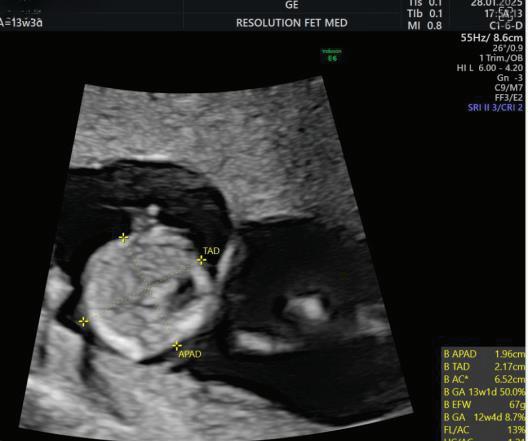

2. NUCHAL TRANSLUCENCY (NT) SCAN

• Done @11–13+6 weeks.

• CRL 45–84 mm.

• This is the cornerstone of first trimester screening.

MEASUREMENTS THAT CAN BE OBTAINED ON

First Trimester Fetal Evaluation:

FETAL ULTRASOUND EXAMINATION AT 11 TO 14 + 0 WEEKS: BASIC BIOMETRY INCLUDES:

Nuchal Translucency

Biperital Diameter

(a) Crown Rump Length(CRL)

(b) Biperital diameter(BPD)

(c) Nuchal Translucency(NT)

DETAILED BIOMETRY INCLUDES:

Along with basic biometry

(a) Abdominal circumference

(b) Head circumference

(c) Femur length

Abdominal Circumference